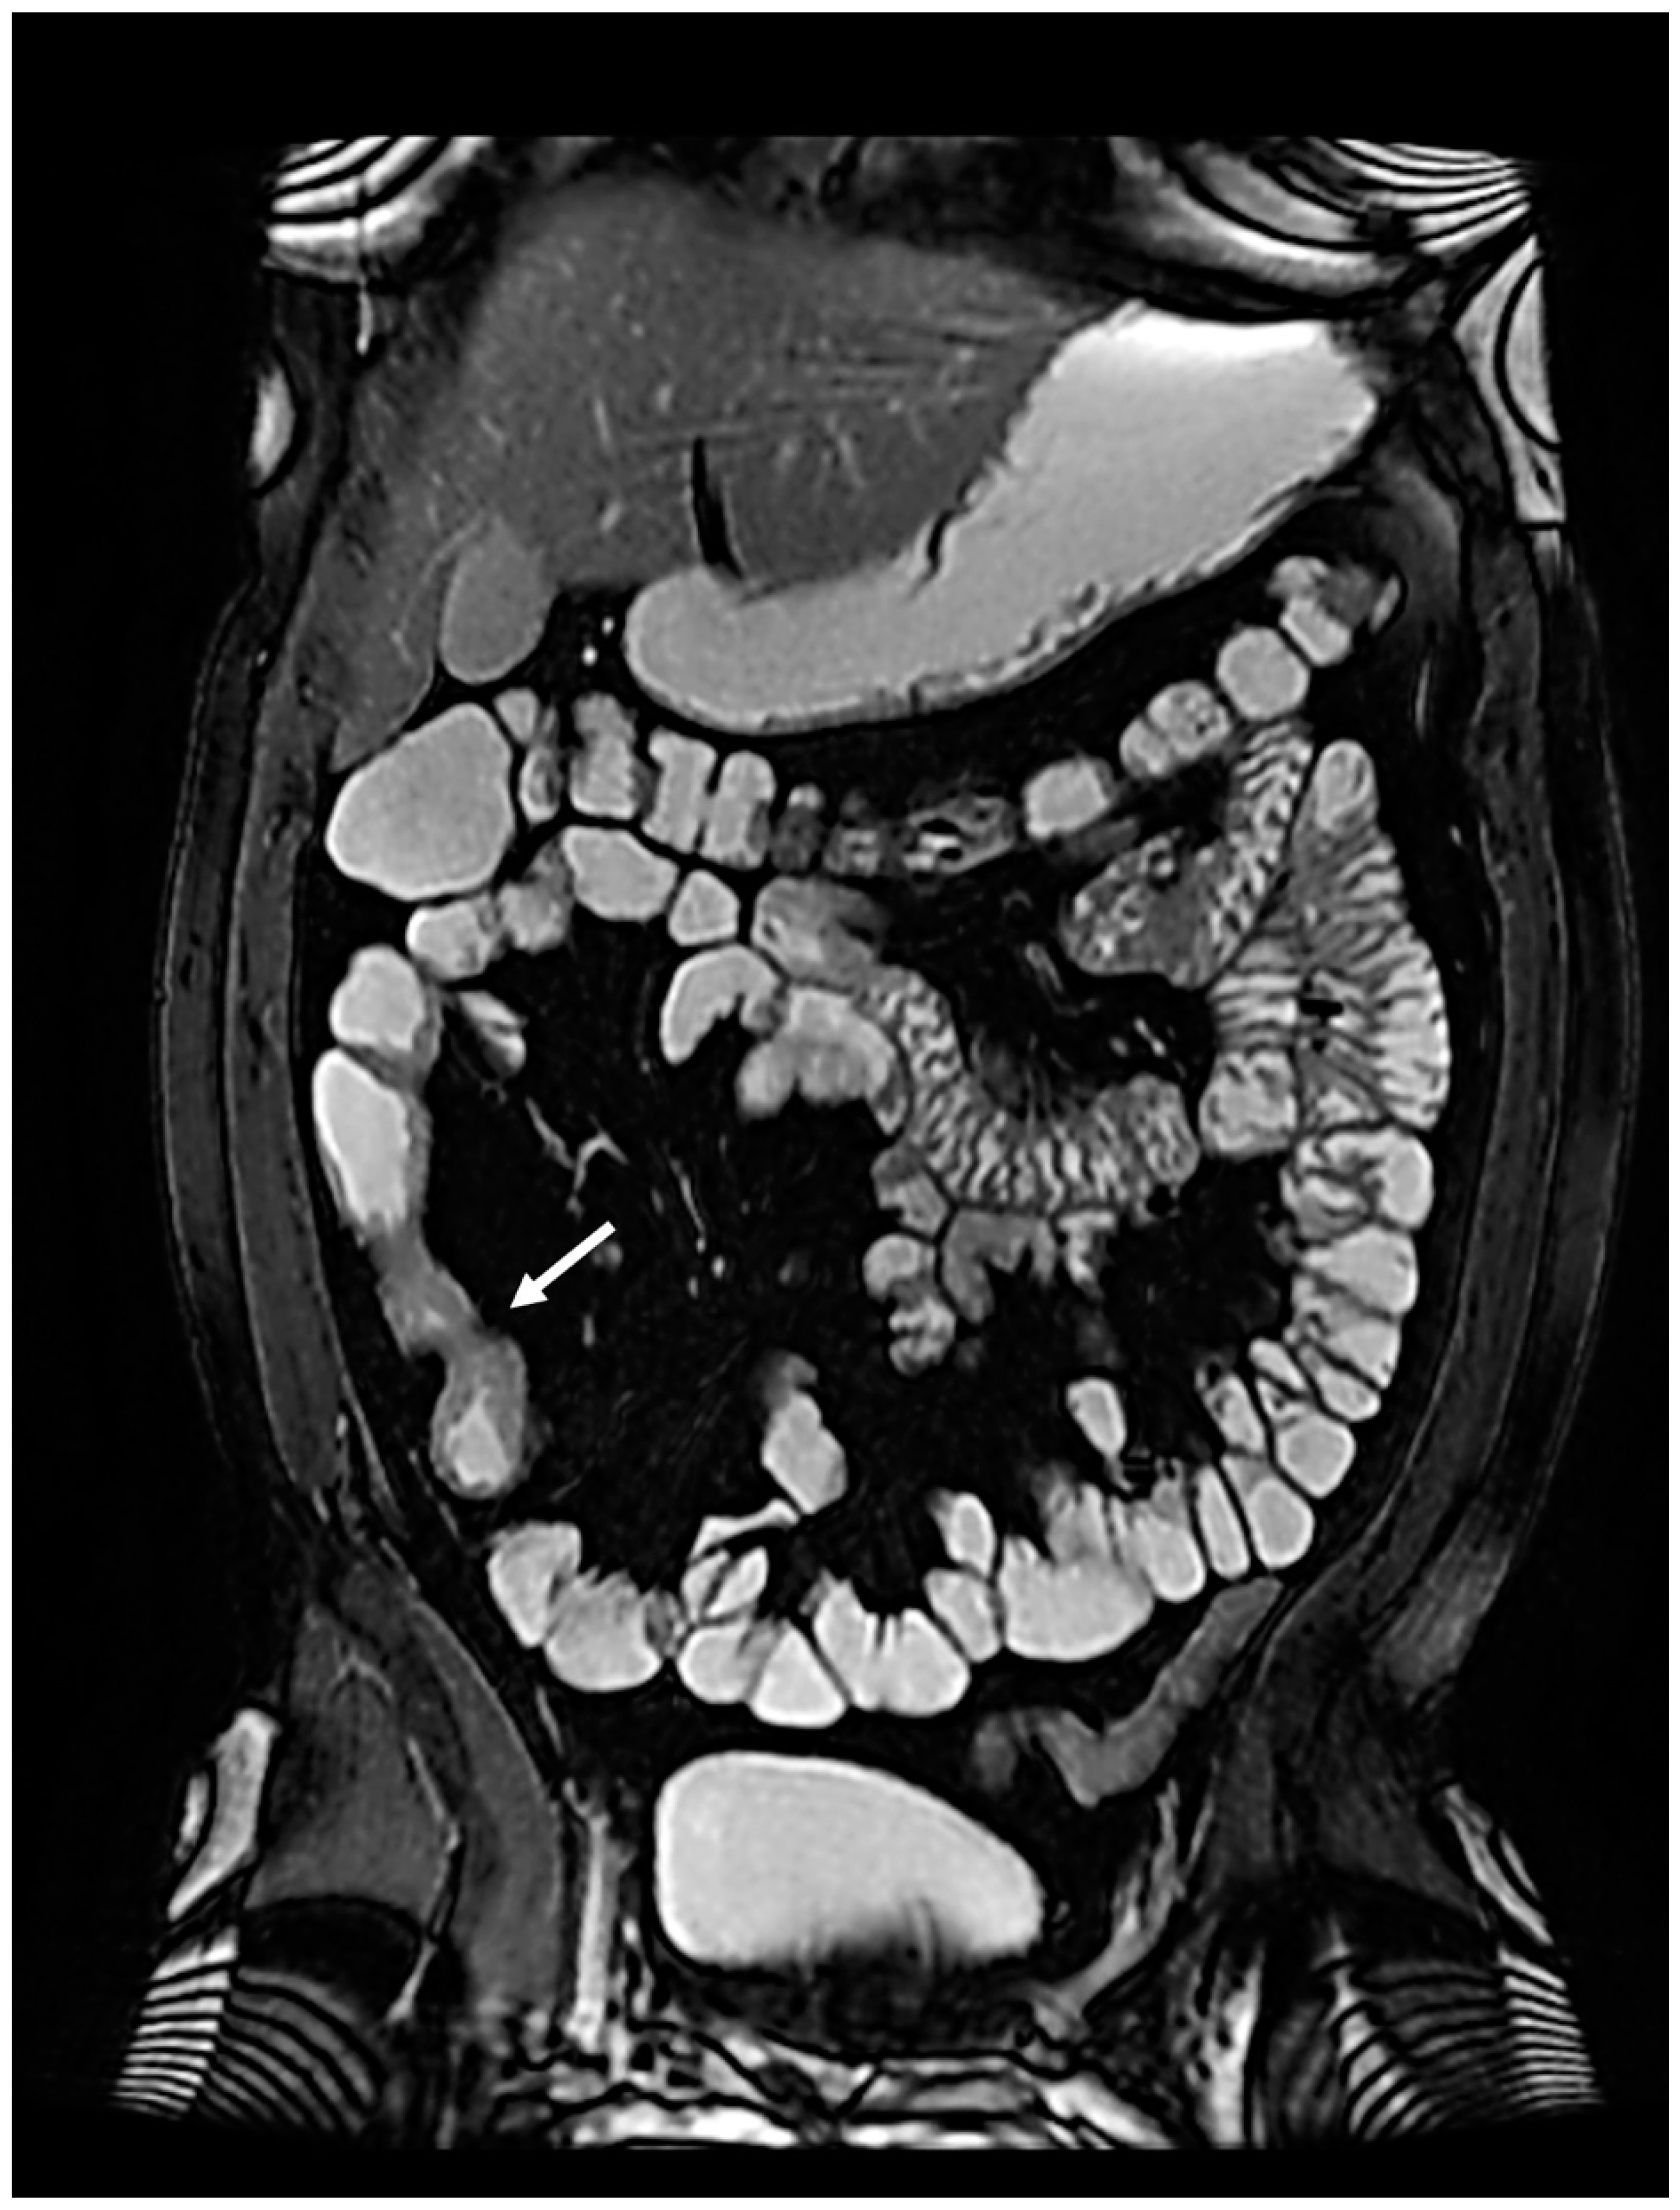

In January 2022, the patient complained of worsening abdominal pain localized in the right low quadrant, so ileo-colonoscopy and MRE were performed again, confirming the presence of stenosis of the terminal ileum and ascending colon (Figure 2).

Figure 2. The suspected stenosing Crohn’s disease at MRE (arrow).